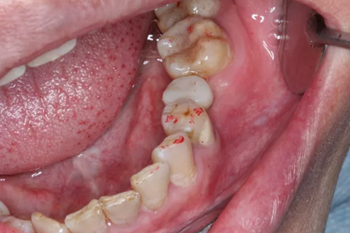

1.試戴臨時(shí)基臺(tái),觀看咬頜位置并且記錄,將基臺(tái)在口外進(jìn)行調(diào)磨。

2.技師即刻對(duì)患者進(jìn)行口內(nèi)掃描,并將數(shù)據(jù)導(dǎo)入到設(shè)計(jì)軟件中,在椅旁設(shè)計(jì)即刻修復(fù)體。

3.臨時(shí)牙數(shù)據(jù)在椅旁切削機(jī)進(jìn)行切削,十幾分鐘后便得到臨時(shí)修復(fù)體。

4.醫(yī)生將臨時(shí)修復(fù)體與臨時(shí)基臺(tái)粘接后并且將其戴到患者口內(nèi)。

5.臨時(shí)修復(fù)體在患者口內(nèi)就位后的狀況。醫(yī)生將咬頜紙放入患者口內(nèi)將臨時(shí)修復(fù)體進(jìn)行觀察調(diào)整。幾乎沒有經(jīng)歷調(diào)磨即可準(zhǔn)確就位。